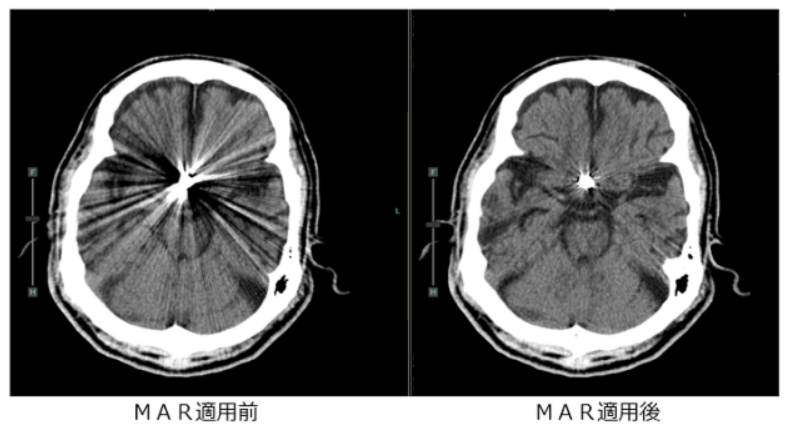

④ 金属アーチファクト低減(MAR)技術により、手術等で体内に挿入した金属の影響でCT検査上見えにくかった臓器の評価ができるようになりました。また血管内に留置したステント内の評価にも役立ちます。